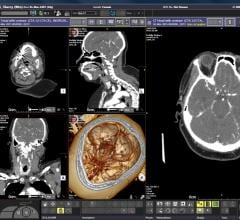

Radiomics is the study of information hidden in imaging exams that machine algorithms are trained to identify to help doctors more accurately diagnose patients, stage cancers, determine optimum therapies, predict patient outcomes or their risk level choose the radiation therapy dose level of risk. The field of medical study extracts large amounts of quantitative features from medical images using data characterization algorithms. These features, called radiomic features, may be able to uncover disease characteristics that fail to be appreciated by the naked eye. It is expected this field will be dominated by artificial intelligence software in the coming years.